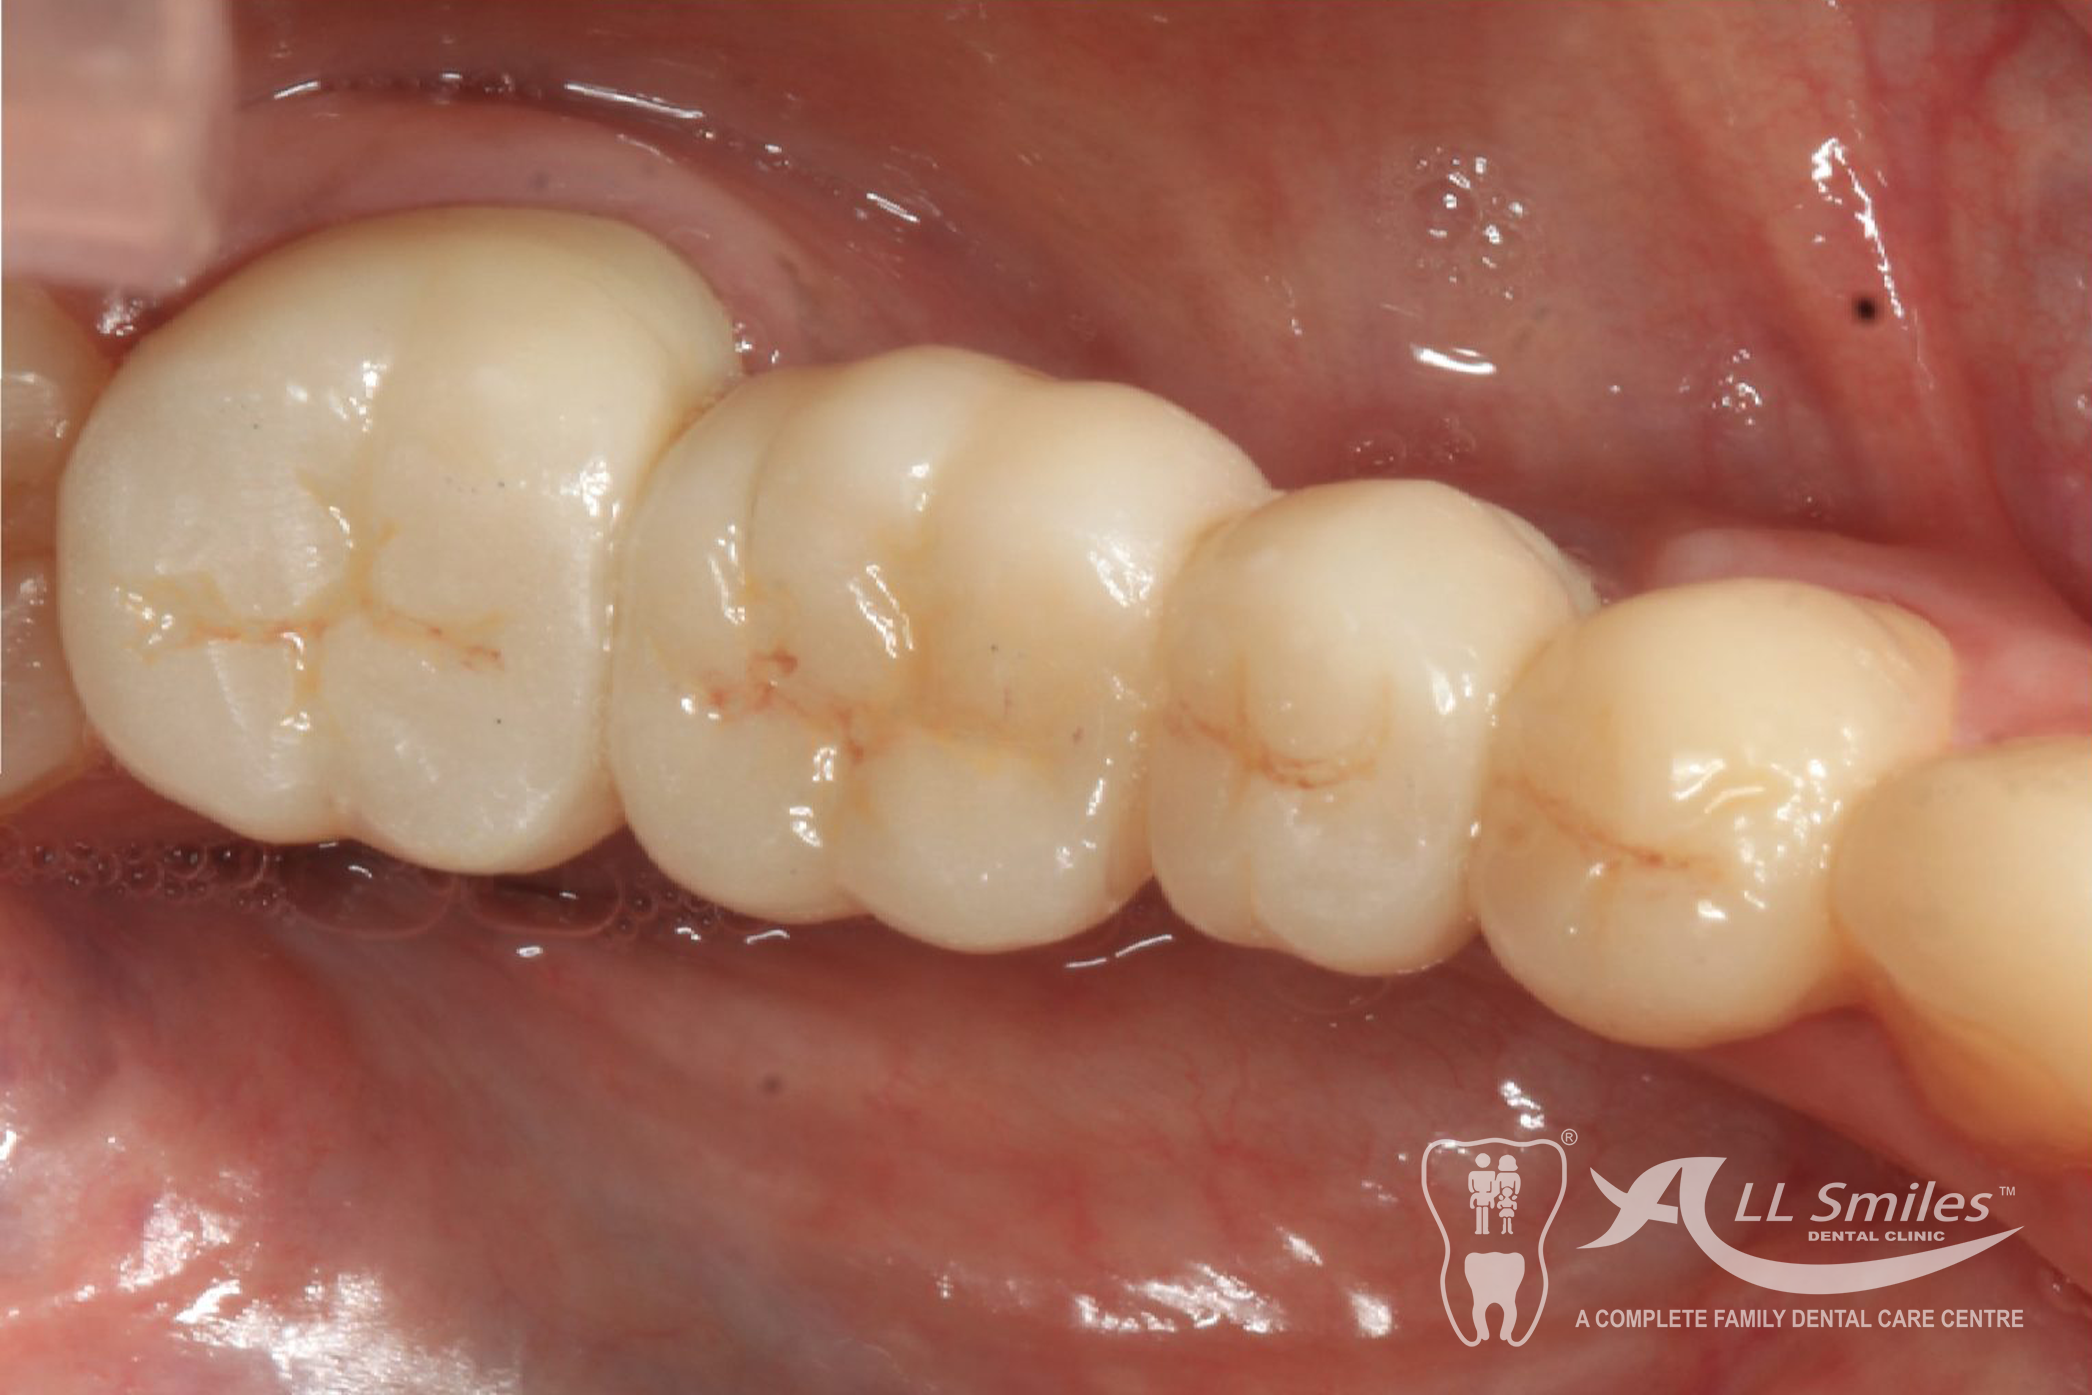

Crowns & Bridges Gallery